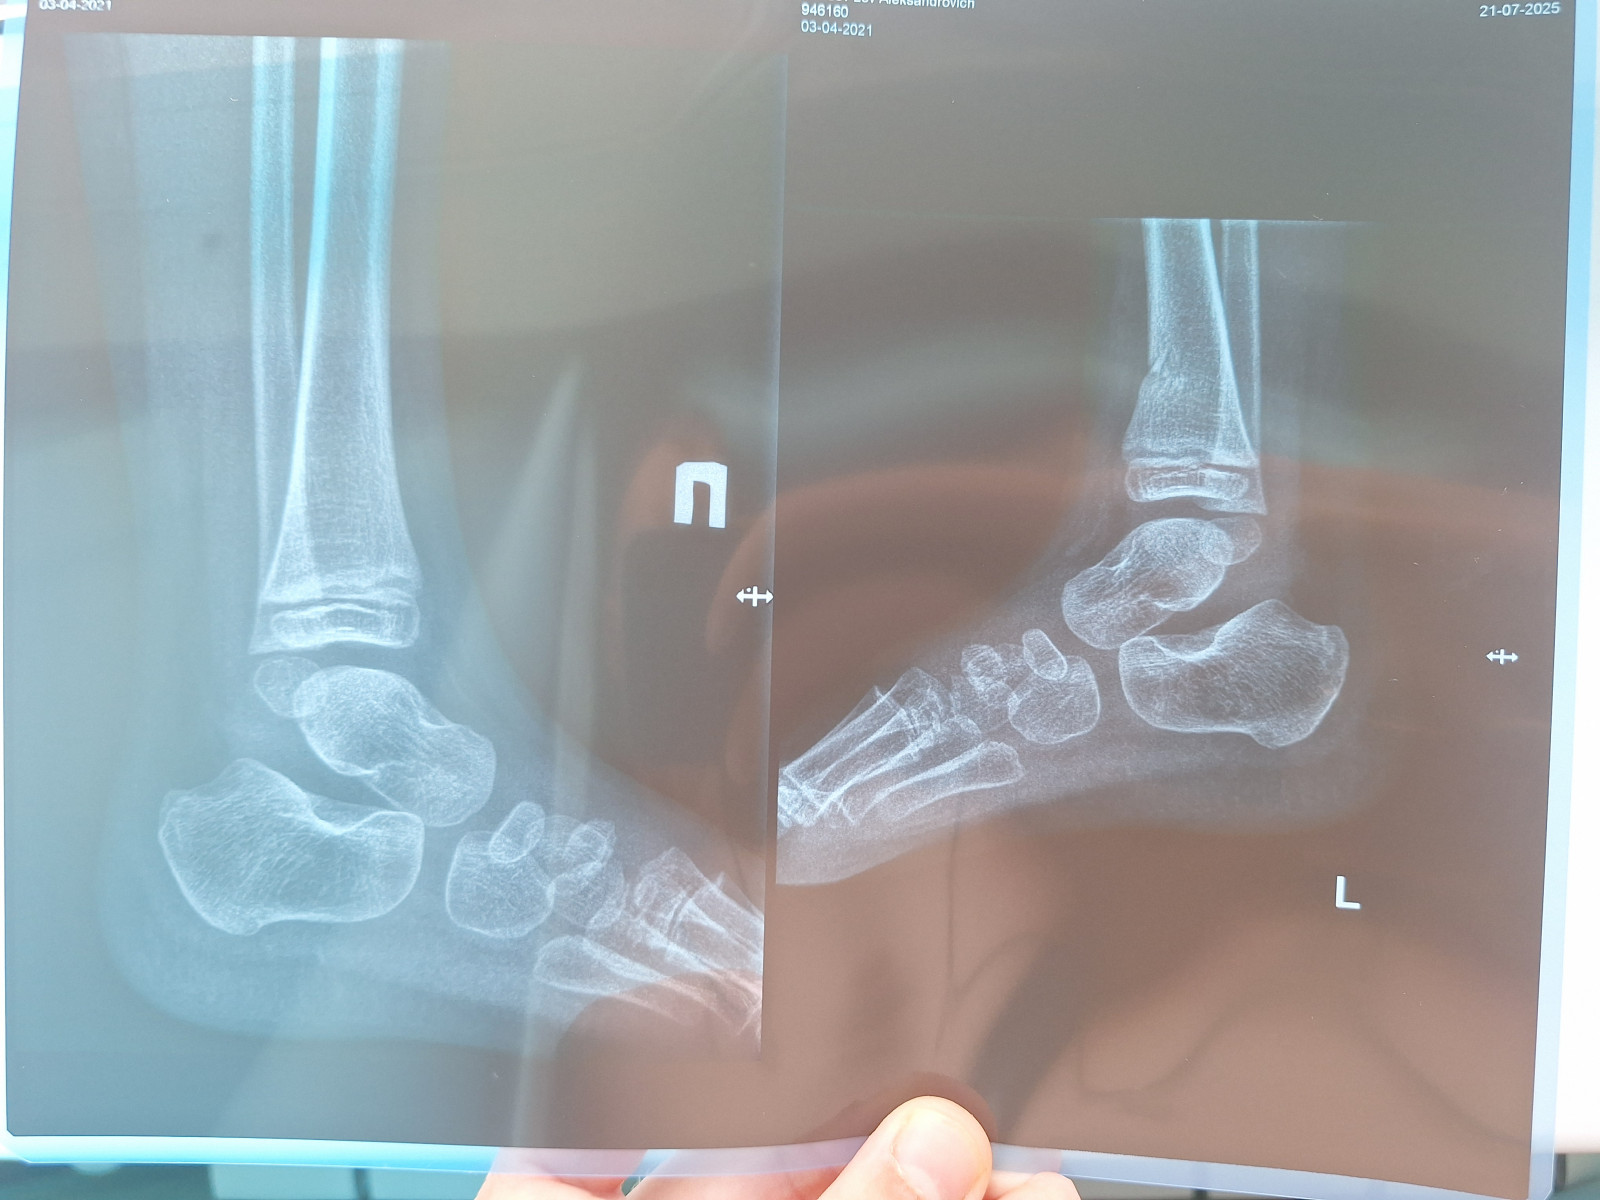

Можно ли снять гипс?   2 ответа

Здравствуйте. Я 11.04.25. сломала левую ногу. Лежала в больнице. Диагноз Перелом проксимального отдела большеберцовой кости закрытый. Закрытый внутрисуставной перелом медиального мыщелка левой большеберцовой кости со смещением отломков. Гемартроз.

Операцию сделали 22.04.25. Обломки сопоставлены. Гипс.

Рекомендовано Иммобилизация 2.5-3 месяца.

Прошло 3 месяца. Рентген прилагаю.

Вопрос: Можно ли мне самой себе снять гипс?